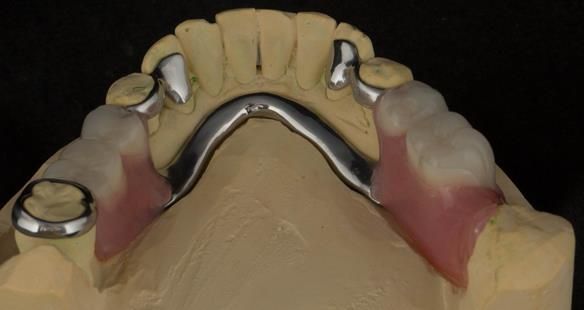

This newsletter describes in step by step detail Angela's transition through immediate partial dentures to crown supported definitive metal based dentures.

The clinical situation and treatment process is shown in detail below with photographs. I (Finlay Sutton) provided the clinical work and Rowan Garstang provided the technical work.